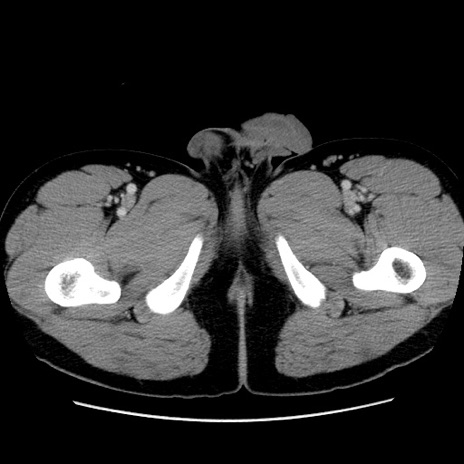

症例4(横断像)

【症例】30歳代男性

【主訴】腹痛、嘔吐

【現病歴】昨晩から突然の腹痛あり、その後嘔吐、軟便も出現。腹痛が改善しないため救急搬送となる。2日前にしめ鯖の食事歴あり。

【身体所見】意識清明、苦悶様、BP 135/90mmHg、BT 35.7℃、腹部:平坦、やや硬、心窩部〜臍部に自発痛、圧痛あり、筋性防御+、反跳痛-

【データ】WBC 8100、CRP 0.57